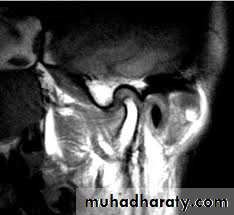

provides evaluation of a variety of hard and soft tissue pathology in the joint which can be done from a single radiation exposure. + CT images provide the most accurate radiographic assessment of the bony components of the joint• magnetic resonance imaging:

• which is most effective diagnostic imaging technique to evaluate TMJ soft tissue (intra-articular soft tissue) and for disk morphology and position with the fact that this technique does not use ionizing radiation is a significant advantagesDiseases of TMJ :A. traumatic arthritis: